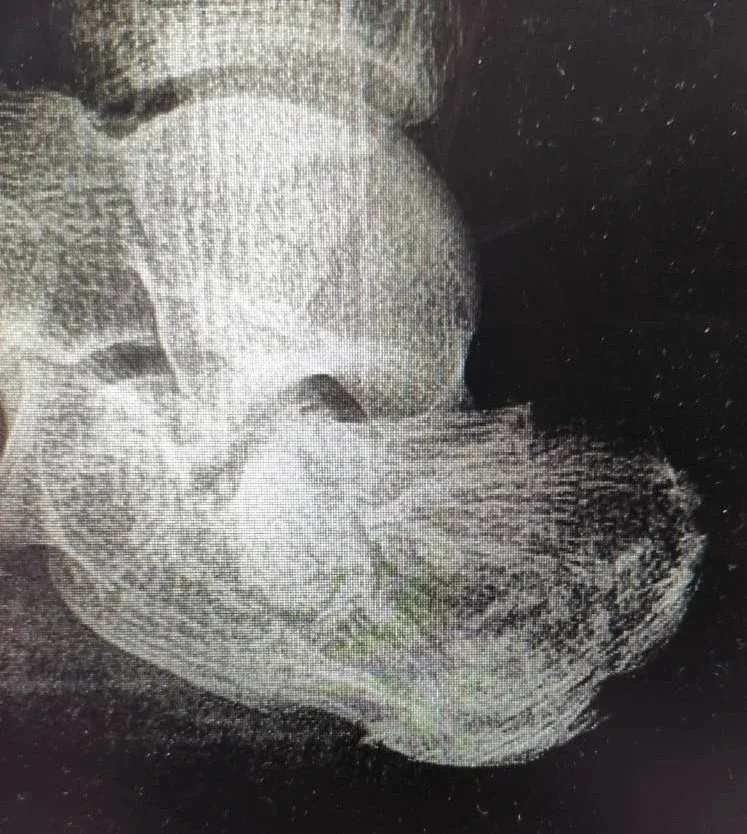

Областной центр спецмедпомощи продолжает помогать жителям региона с тяжёлыми травмами костей и суставов. В первую рабочую неделю нового года врачи провели операции 2 пациентам с переломом пяточной кости. Такие травмы считаются сложными и требуют точной работы хирургов.

Главная цель вмешательства – сохранить подтаранный сустав и вернуть ему подвижность. Если операцию не сделать, после такого перелома почти сразу появляется сильная боль. В итоге человеку приходится фактически «выключать» сустав, полностью лишая его движения, чтобы хоть как-то справляться с болью.

Врачи восстановили правильное положение костей и стабилизировали сустав. Сейчас самый сложный послеоперационный этап уже позади. Пациенты чувствуют себя стабильнее и начали проходить курс восстановления, который поможет постепенно вернуться к обычной жизни и опоре на ногу.